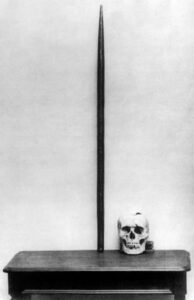

Una parte del trabajo que se realizaba consistía en romper las rocas demasiado grandes para que pudiesen moverse. Para ello, se perforaban, se rellenaba el hueco con dinamita, se cubría con arena y se prensaba delicadamente. Con esto se conseguía que la explosión fuera algo más que fuegos de artificio. Sin embargo, ese día 13 hizo honor a su fama de mala suerte y algo no salió como se esperaba. Parece ser que Phineas no prestó mucha atención y procedió a prensar sin haber colocado la arena. El resultado: la vara de metal que usaba salió despedida y atravesó su cráneo entrando por la mejilla izquierda y saliendo por la parte frontal craneal.

Sorprendentemente, Phineas Gage no sólo no murió en ese instante, si no que se mantuvo consciente en todo momento. Fue trasladado por sus compañeros al hotel donde acudió el doctor Harlow. La herida se describió como un embudo invertido en la parte superior de la cabeza, y la abertura rondaba los 4 cm de diámetro. Reseñable fue su supervivencia a dicho accidente, apareciendo en un buen puñado de periódicos de la época con lúgubres titulares encabezándolo, pero aún más increíble fue que mantuviera capacidad para moverse, hablar y responder de forma coherente, apenas habiendo transcurrido unos minutos del suceso. La única secuela que se podía observar a simple vista era la pérdida del ojo izquierdo. En unos dos meses Phineas ya estaba «oficialmente» curado. Pero algo había cambiado en él, en lo profundo de su ser. Ya no volvería a ser el mismo.

A pesar de que la recuperación tanto física como sensitiva fue completa, Phineas Gage ya no era Phineas Gage. Como relataba el doctor Harlow «se había destruido el equilibrio que había entre su facultad intelectual y sus propensiones animales». El hombre con energía de carácter, hábitos moderados y de cierto éxito que dirigía a un grupo de hombres en la construcción del ferrocarril con alta estima de los jefes dio paso a otro, sin orden, maleducado, caprichoso y sin capacidad alguna para la planificación y la preparación. Tal fue el cambio que fue despedido poco después porque consideraron que la variación en su mente era demasiado acentuada. El problema era su carácter, no sus conocimientos y tampoco su físico.Durante una época cambió de trabajo cada poco, abandonándolos normalmente por arrebatos o incumplimientos en el mismo. Acabó siendo exhibido en el Museo de Barnum, en Nueva York, siempre acompañado del hierro de atacar.

Las zonas en cuestión afectadas fueron las cortezas prefrontales de ambos hemisferios, en las caras ventrales e interiores, conservando las laterales. Esta región parece clave en la toma de decisiones, explicando en parte la vida tras el accidente, su incapacidad para seguir las reglas sociales, planificar el futuro y saber elegir lo más beneficioso para él. Aunque es obligatorio decir que ni siquiera hoy día hay un consenso total sobre estos procesos y sus áreas, habiendo todavía mucho por descubrir.